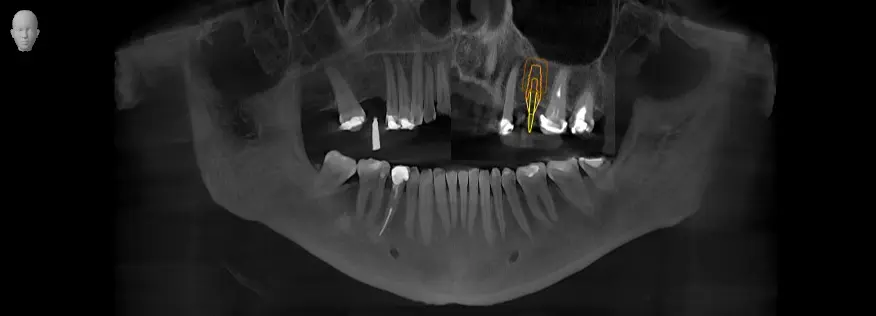

TOMOGRAFÍA PARA ENDODONCIA

Evaluación necesaria en campo reducido para visualizar los conductos radiculares o probables fracturas.